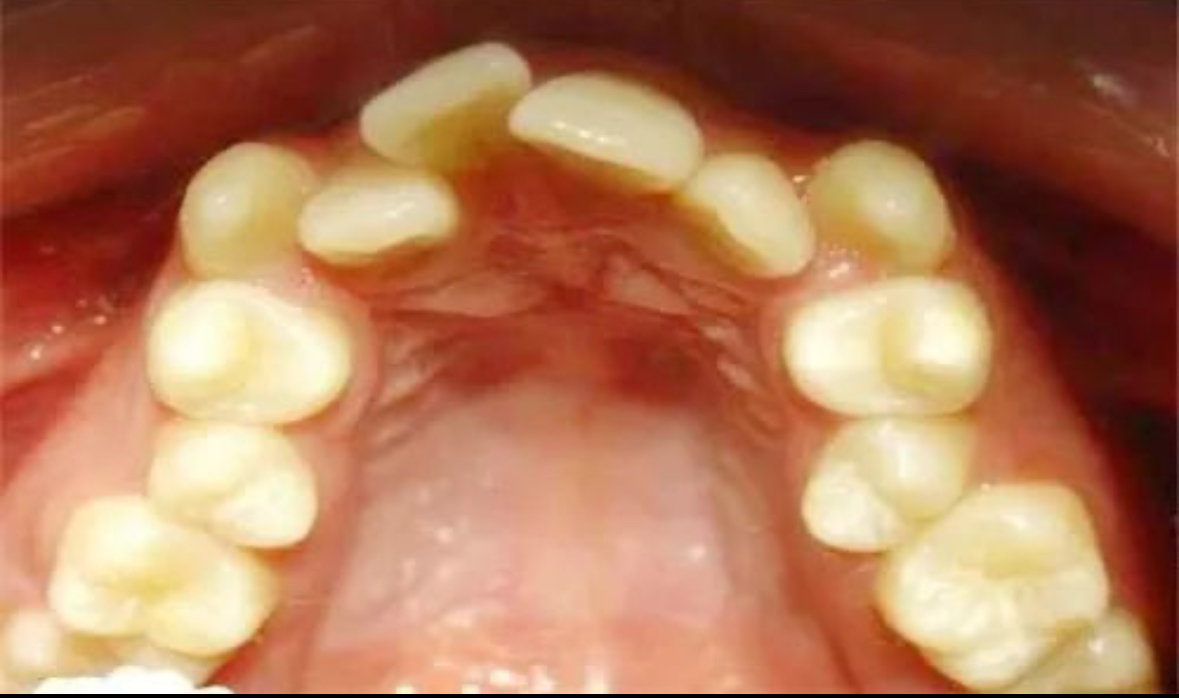

牙齒不齊矯正技術大盤點哪種適合你

牙齒不齊不僅影響美觀,還可能引發一系列口腔健康問題。幸運的是,現代牙科技術提供了多種解決方案來幫助改善這一狀況。下面珠海六和口腔醫院就來盤點一下目前主流的幾種牙齒不齊矯正技術,并探討哪一種最適合你的需求。